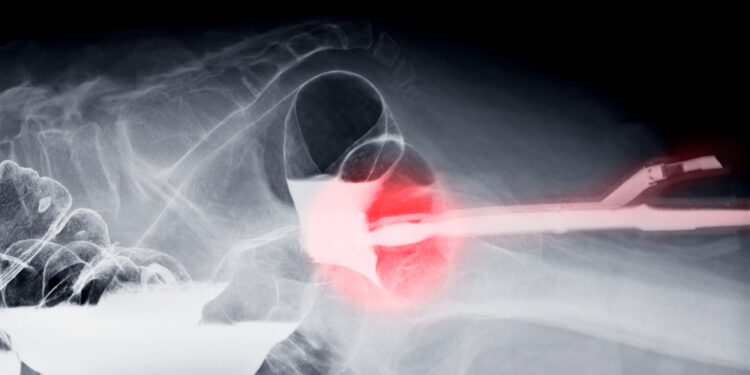

Bario sulfatas dažniausiai suleidžiamas klizmos būdu į tiesiąją žarną. Gydytojas ar slaugytojas paaiškins, kaip reikėtų pasiruošti šiam tyrimui. Jei instrukcijų negavote ar jos neaiškios, prieš procedūrą pasitarkite su gydytoju.